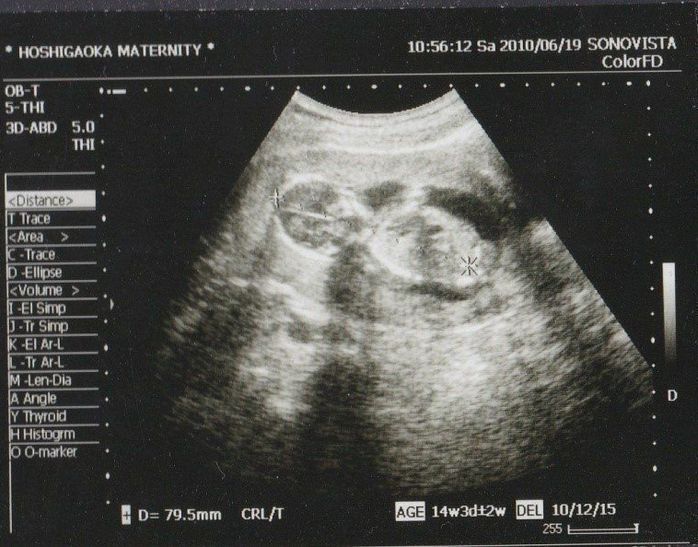

妊娠14週目のエコー写真

頭からお尻までの大きさが79.5mmにまで成長しました。左側に頭で右側が体です。腕らしいものも写っています。この週から待ちに待った経腹法でのエコー撮影でした。経膣法とは違い気分的にとても楽ちんでした。